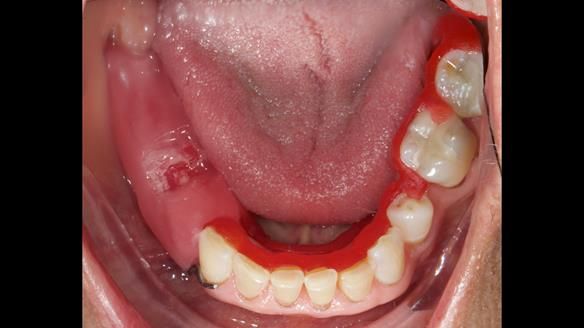

Joyce's Case Presentation 61

Welcome to Newsletter 61. In this edition, I walk through the process of creating and fitting a metal based lower partial denture for Joyce, a fit and healthy 76 -year-old woman.

The missing lower right teeth to be replaced with a metal based partial denture.

Soft Tissue Examination: Routine visual screening for oral cancer was conducted, and the soft tissues appeared healthy.

The detailed clinical situation and treatment process are outlined below, with clinical work provided by me and technical work by Rowan Garstang. The treatment spanned six visits for denture fitting and one review.